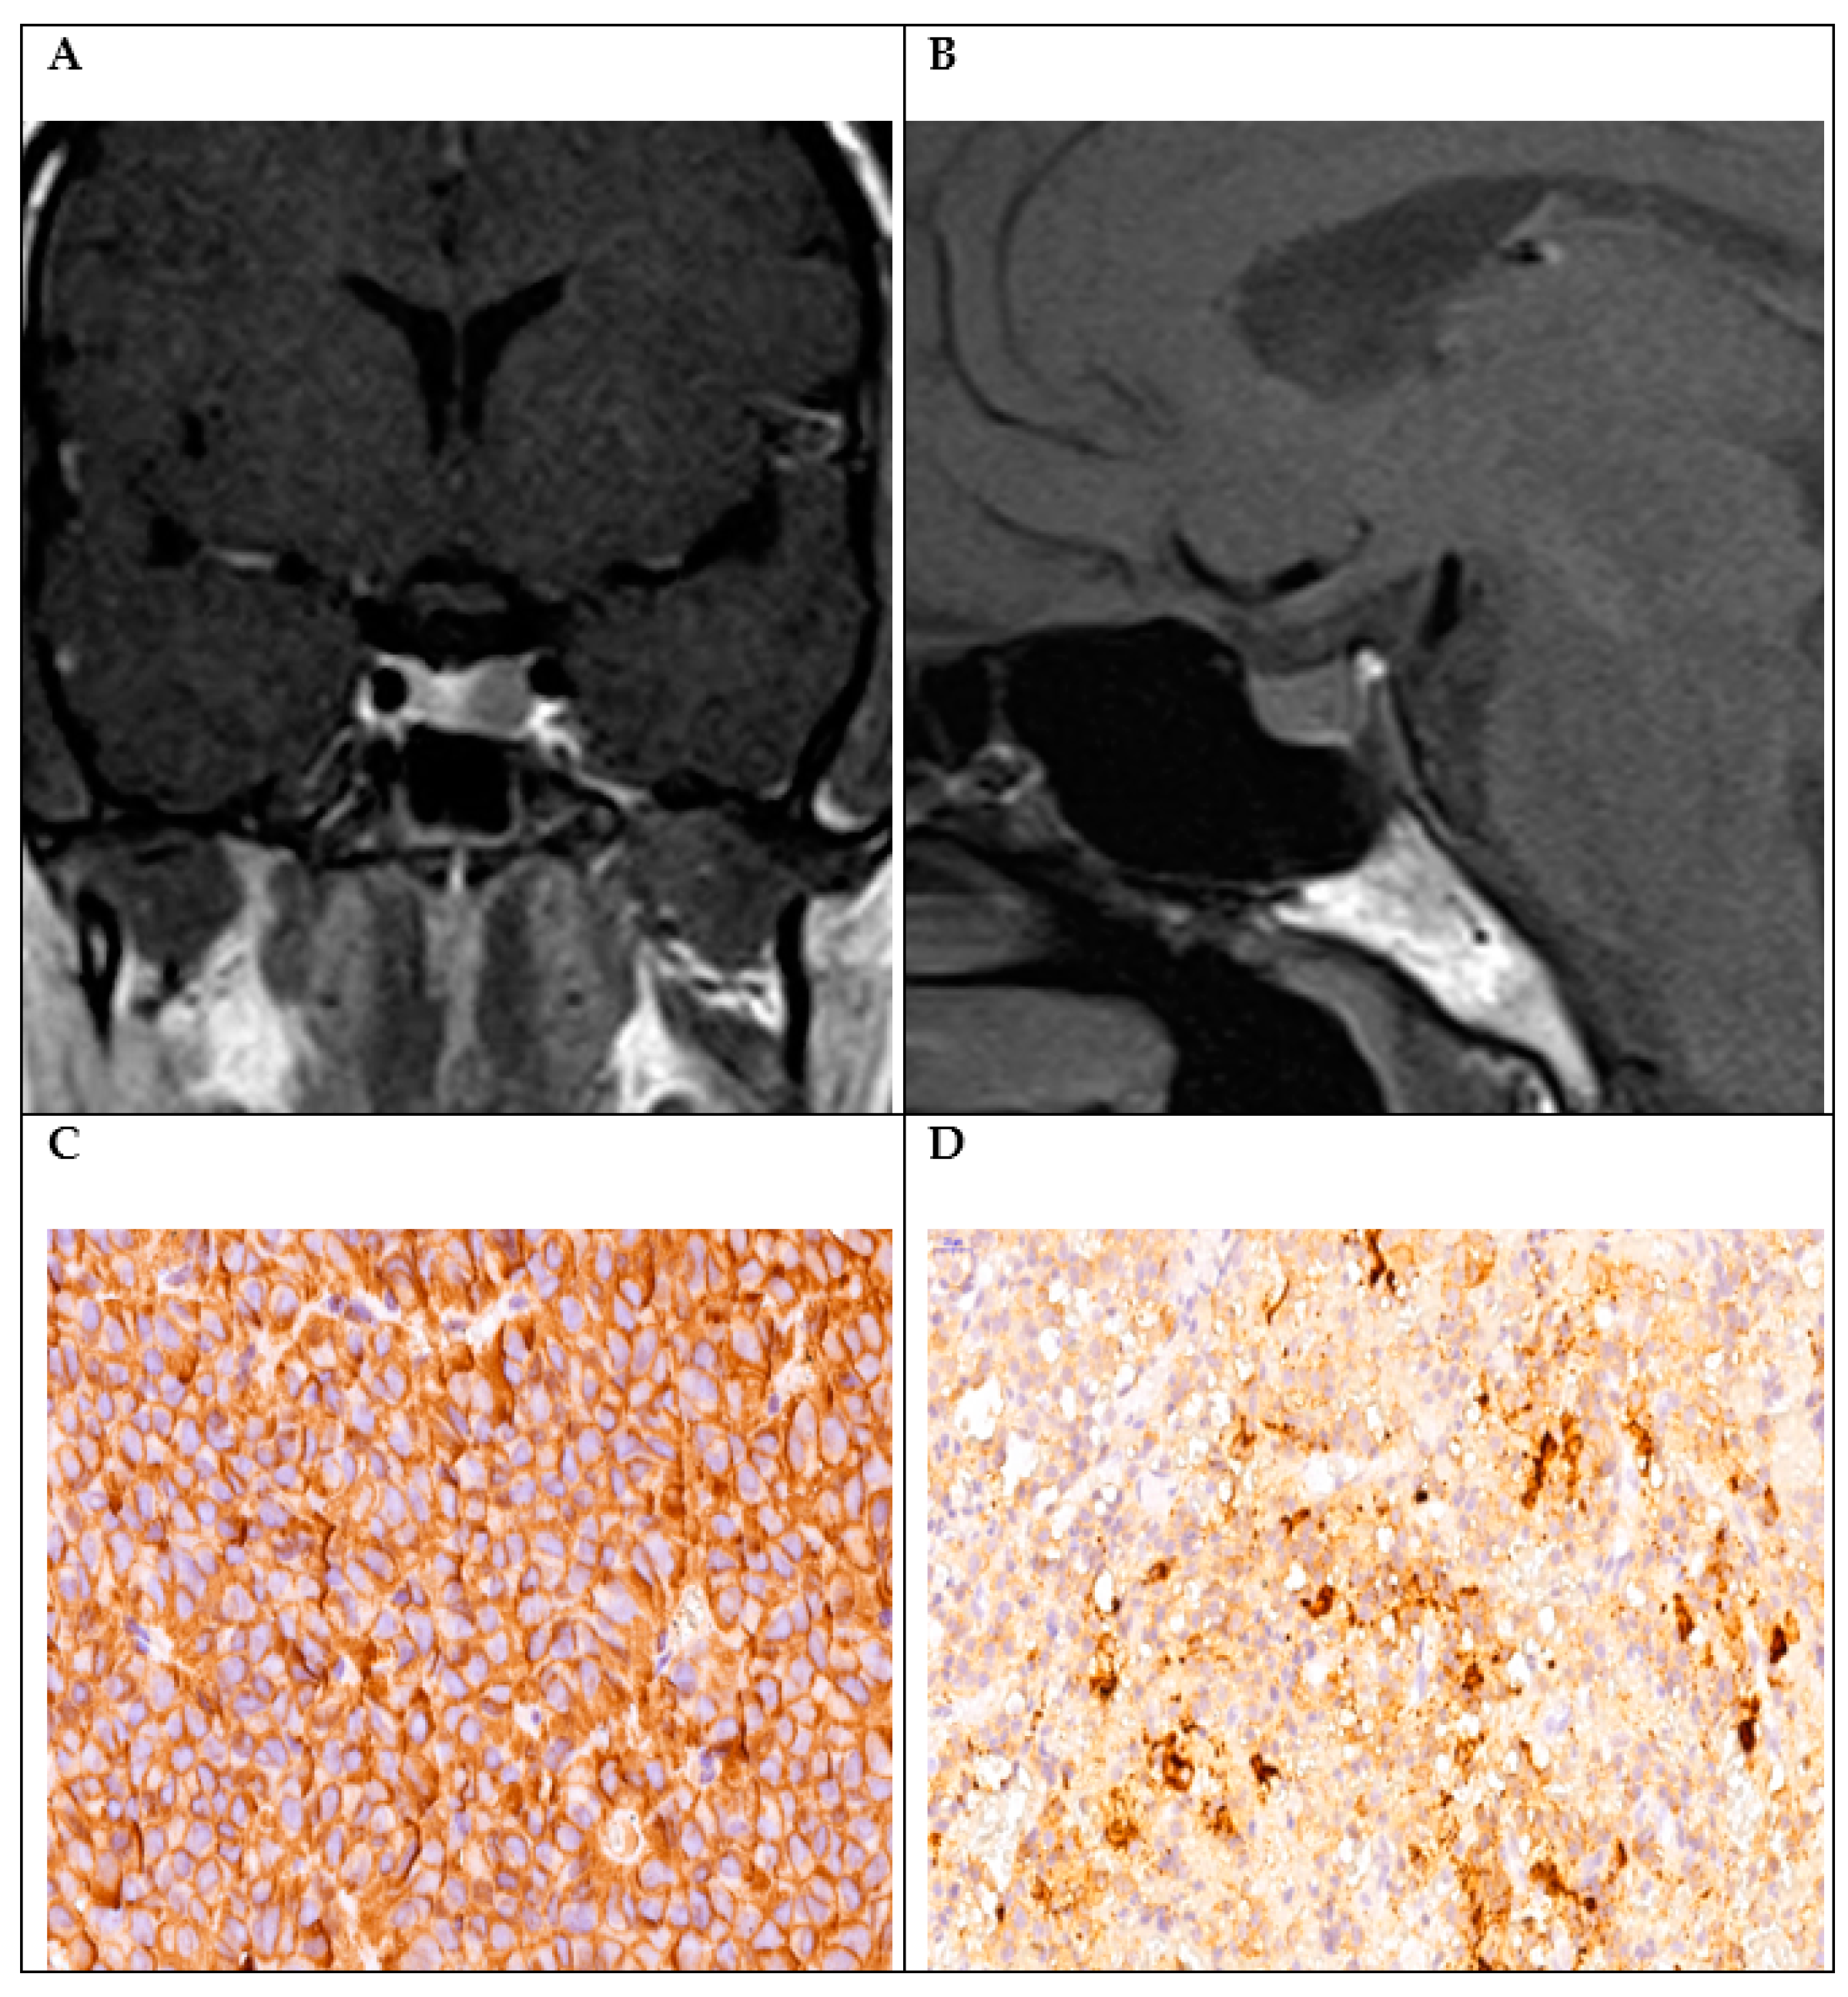

| 2 | GH + PRL + ACTH + LH | 44, Female | Acromegaly Hyperprolactinemia Subclinical Cushing’s | Microadenoma | IGF, GH, PRL, ACTH, and cortisol | GH PRL ACTH LH | 0 |

| 6 | GH + ACTH | 50, Female | Acromegaly | Macroadenoma Cavernous sinus invasion | IGF1 | GH (+3) ACTH (+1) | 1 |